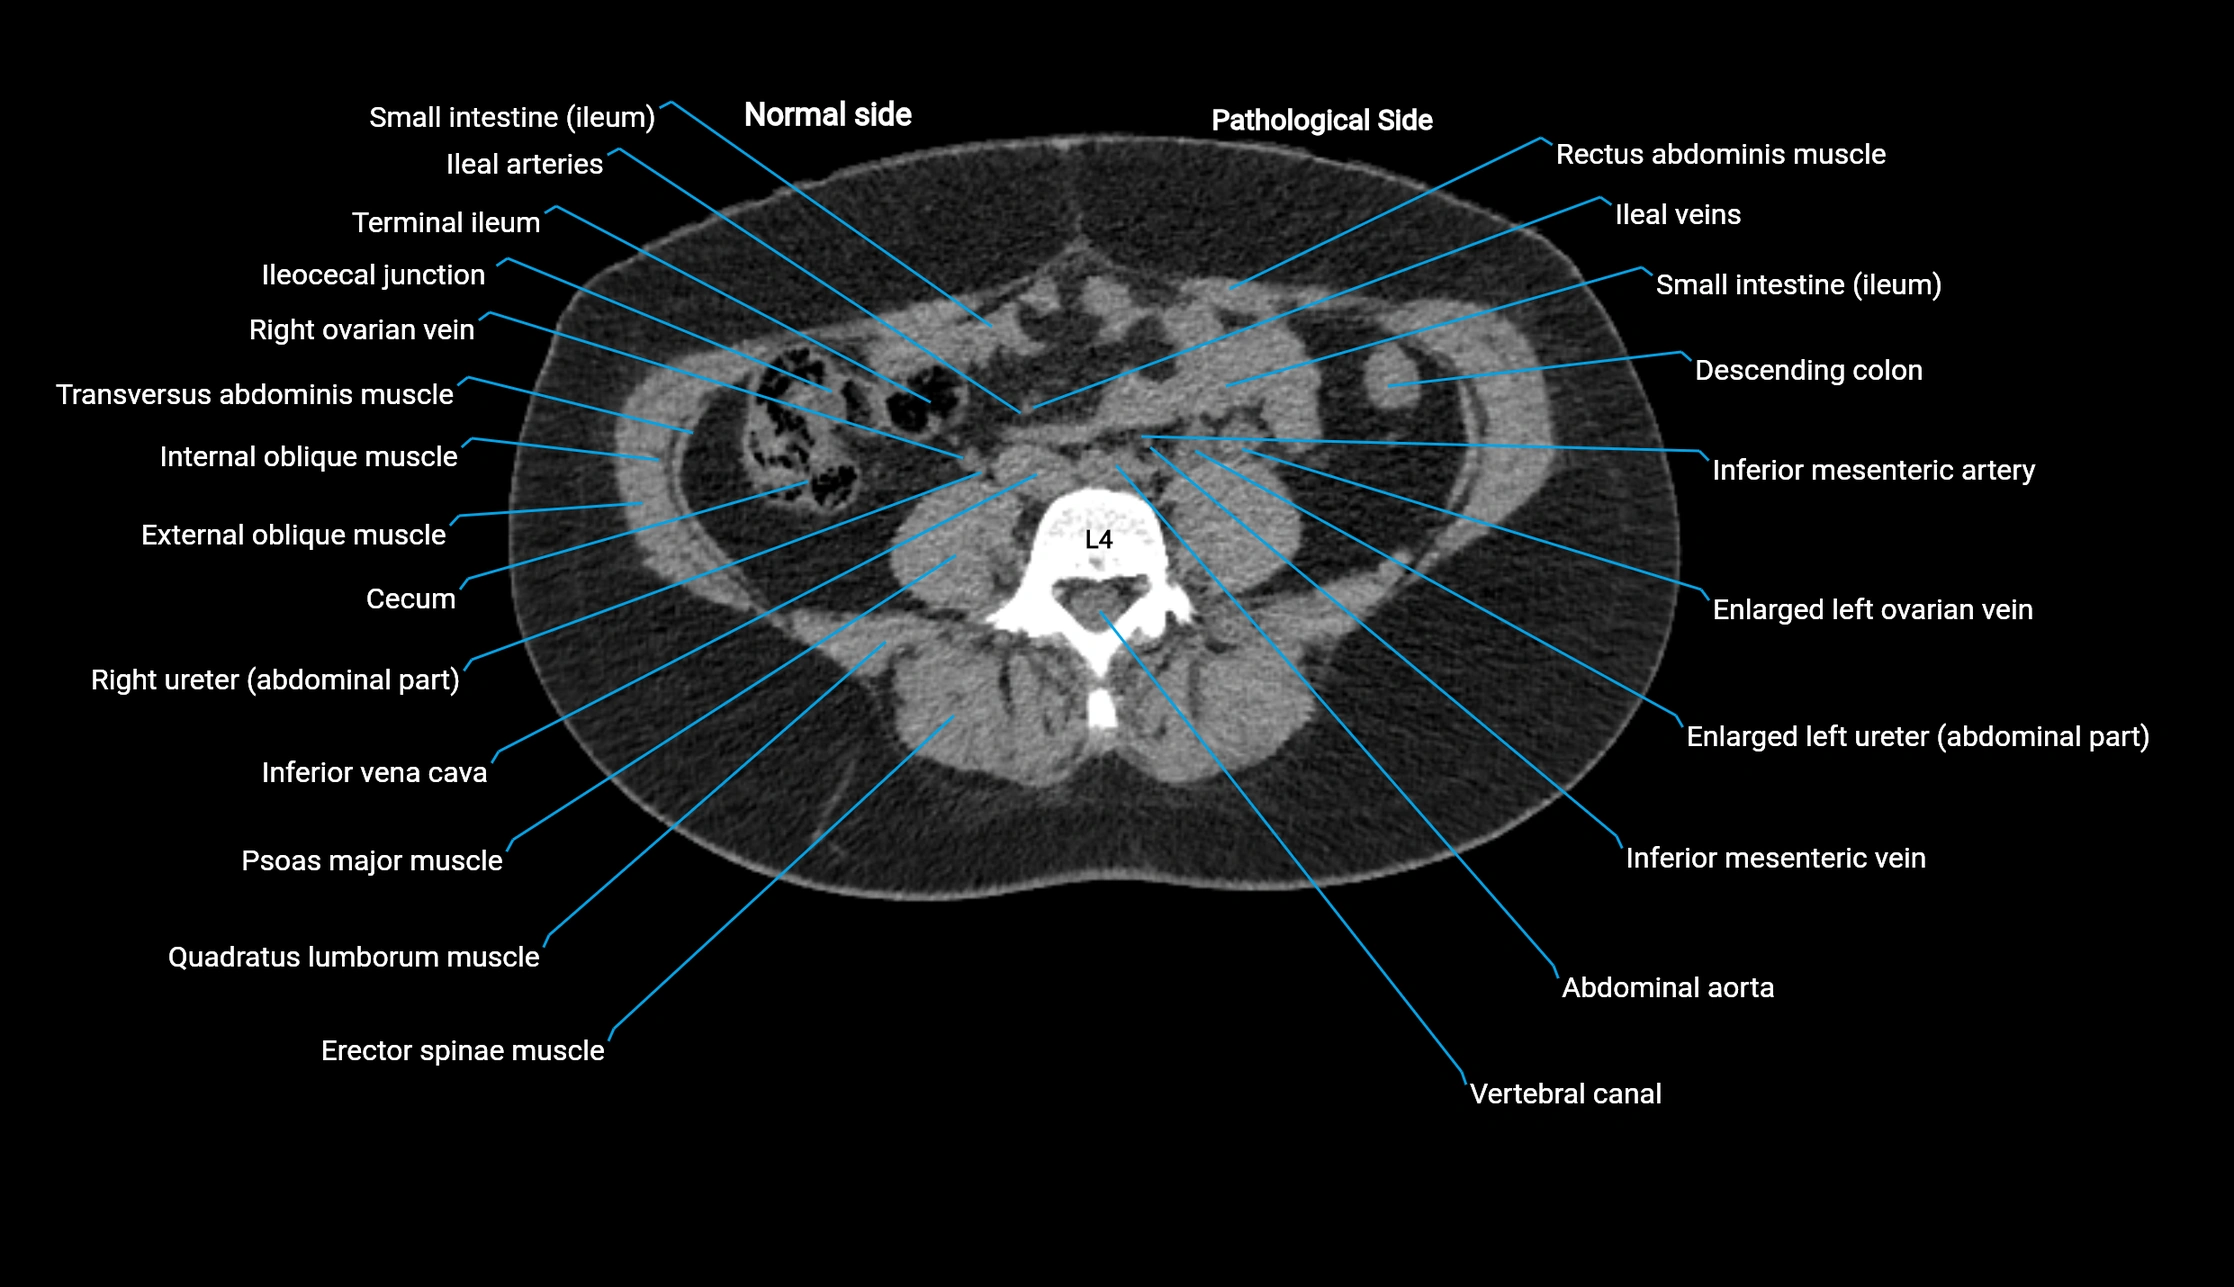

CT image

image